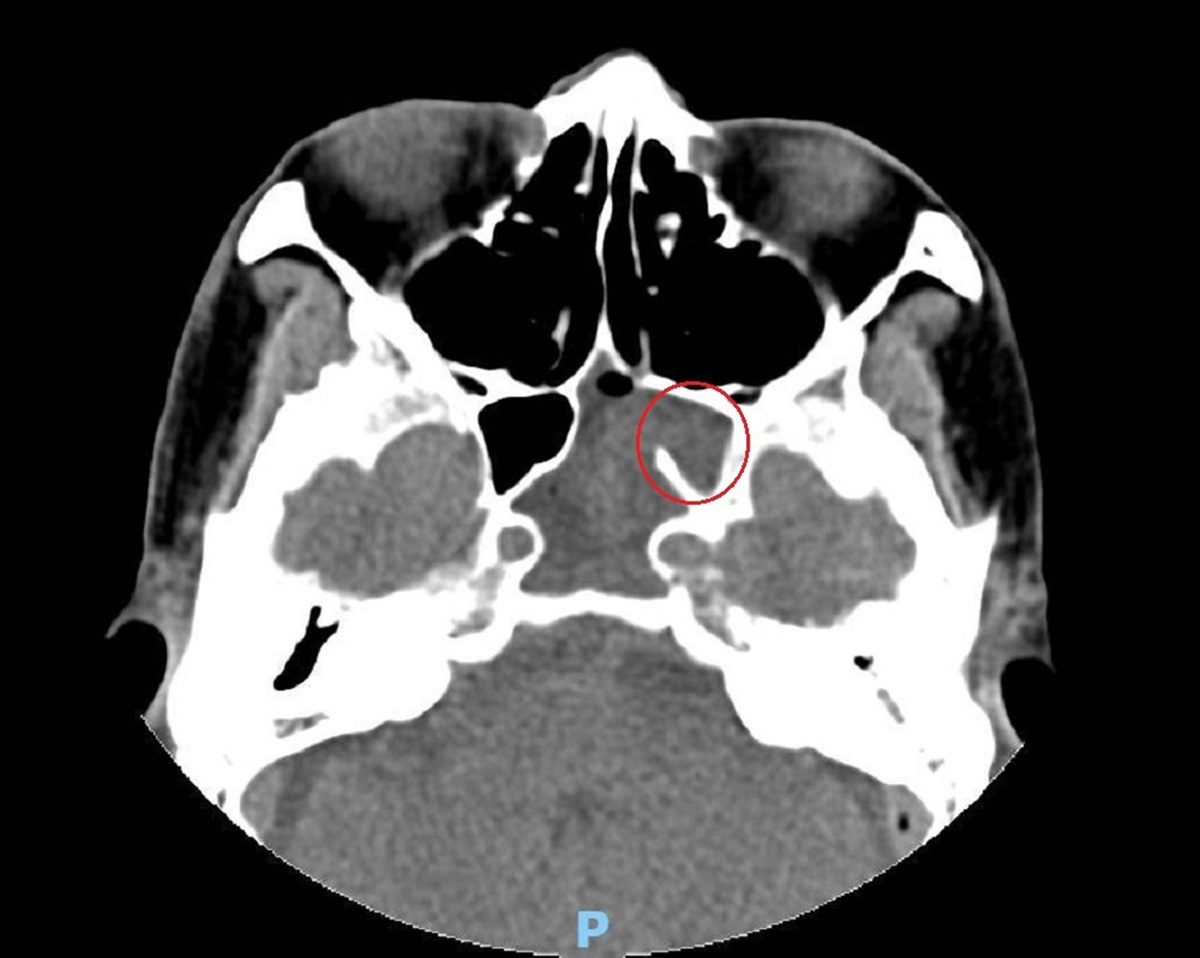

▲加護病房主任林文培說,懷疑李先生是腦膜炎,經檢查及病程情況予以排除,再經電腦斷層及核磁共振攝影,發現其鼻腔最深處的左側蝶竇不正常顯影。(圖/彰化醫院提供)

加護病房主任林文培說,懷疑李先生是腦膜炎,經檢查及病程情況予以排除,再經電腦斷層及核磁共振攝影,發現其鼻腔最深處的左側蝶竇不正常顯影,疑似佈滿膿瘍,壓迫到第3至第6對腦神經,才出現頭痛、複視等各種症狀,會診神經內科及耳鼻喉科。